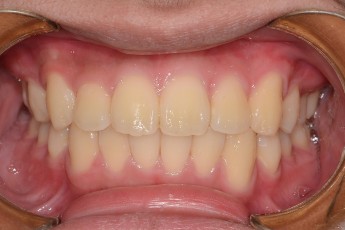

Before

After